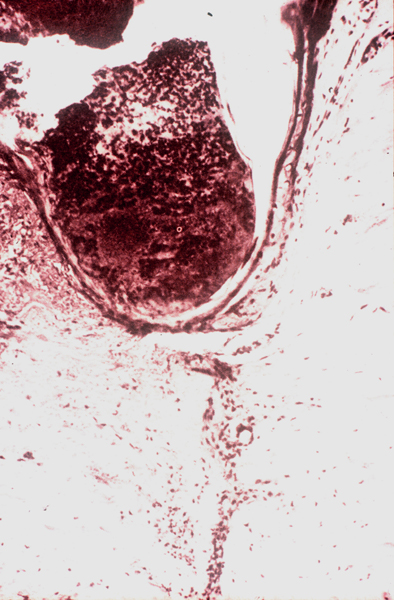

Imágenes histológicas

cicatriz01p.JPG (321749 bytes) cicatriz02p.JPG (492337 bytes) cicatriz03p.JPG (236643 bytes)